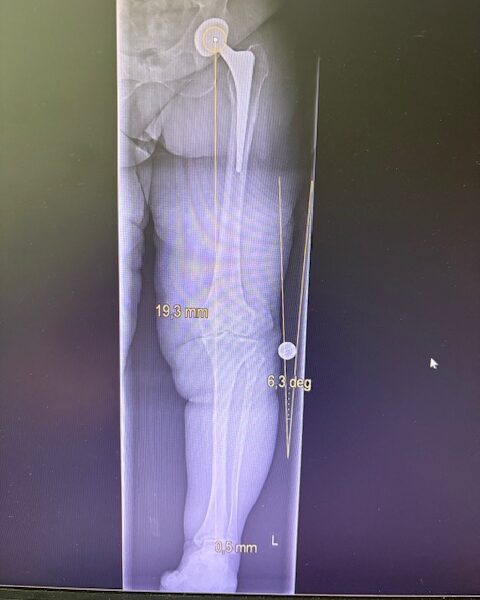

Ο προεγχειρητικός ψηφιακός σχεδιασμός

Πραγματοποιήθηκε σε ειδική ακτινογραφία ολόκληρων των δύο κάτω άκρων. Σε αυτό το ψηφιακό μοντέλο σχεδιάστηκε με ακρίβεια το είδος, το μέγεθος και η ακριβής θέση των προθέσεων, με βάση τα ανατομικά χαρακτηριστικά της ασθενούς.

Ο ψηφιακός σχεδιασμός επιτρέπει απόλυτη εφαρμογή των μοσχευμάτων, ελαχιστοποιώντας τα περιθώρια απόκλισης και εξασφαλίζοντας άριστη ευθυγράμμιση και κινηματική ισορροπία του γόνατος.